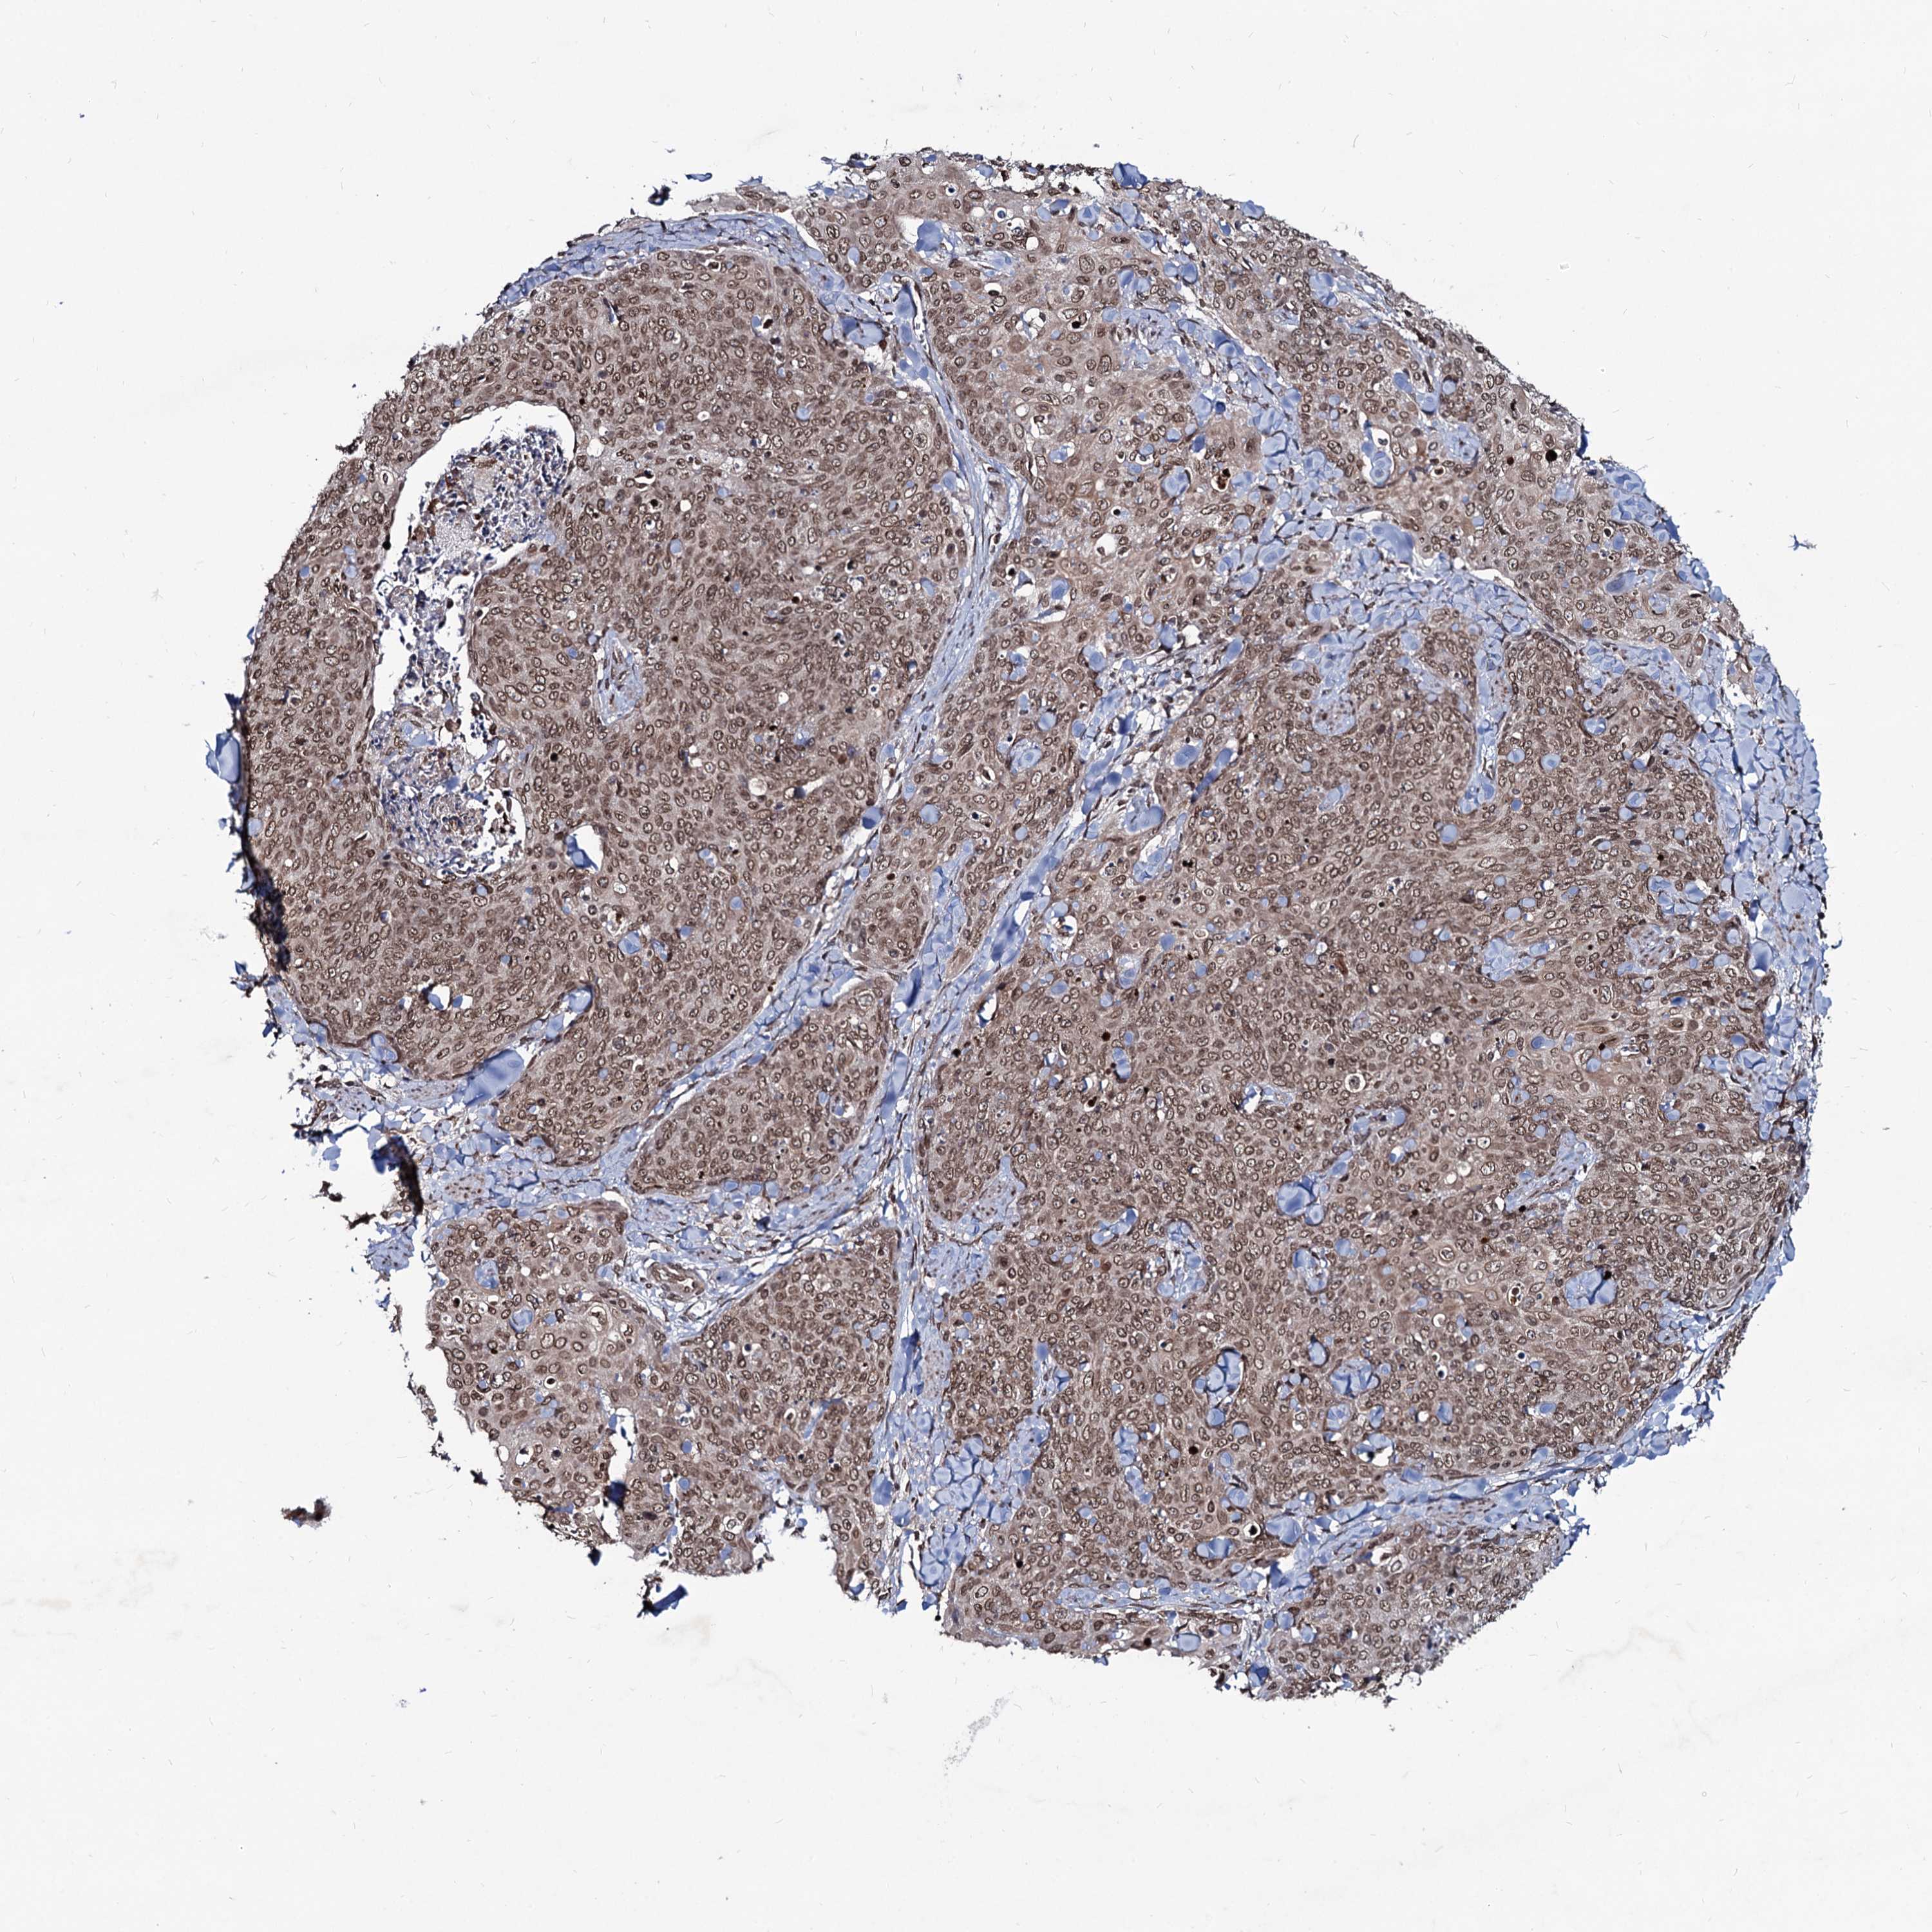

Basal cell and squamous cell cancer

SKIN CANCER - Protein expressioni

A mouse-over function shows sample information and annotation data. Click on an image to view it in a full screen mode. Samples can be filtered based on level of antibody staining by selecting one or several of the following categories: high, medium, low and not detected. The assay and annotation is described here.

Each image is clickable and will lead to virtual microscopy that enables deeper exploration of all samples and also displays staining intensity scores, fraction scores and subcellular localization as well as patient and tissue information for each sample.

Antibody HPA039343

Basal cell carcinoma

Squamous cell carcinoma, NOS

Squamous cell carcinoma, metastatic, NOS